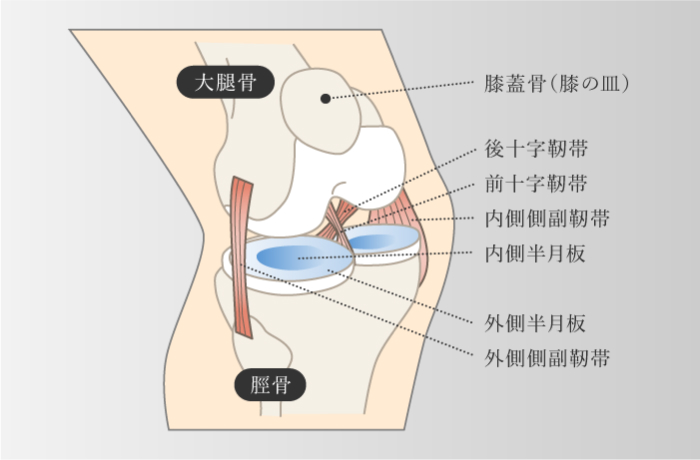

膝の靭帯損傷

前十字靭帯・後十字靭帯・内側側副靭帯・外側側副靭帯

膝の靭帯損傷

前十字靭帯・後十字靭帯・内側側副靭帯・外側側副靭帯

-

膝関節は、前十字靭帯、後十字靭帯、内側側副靭帯、外側側副靭帯の4本と2種類の軟骨で構成されている。上記4本の靭帯損傷はスポーツや外傷など、膝に強い力がかかった場合に起こり、その力の方向によって損傷する靭帯が異なる。